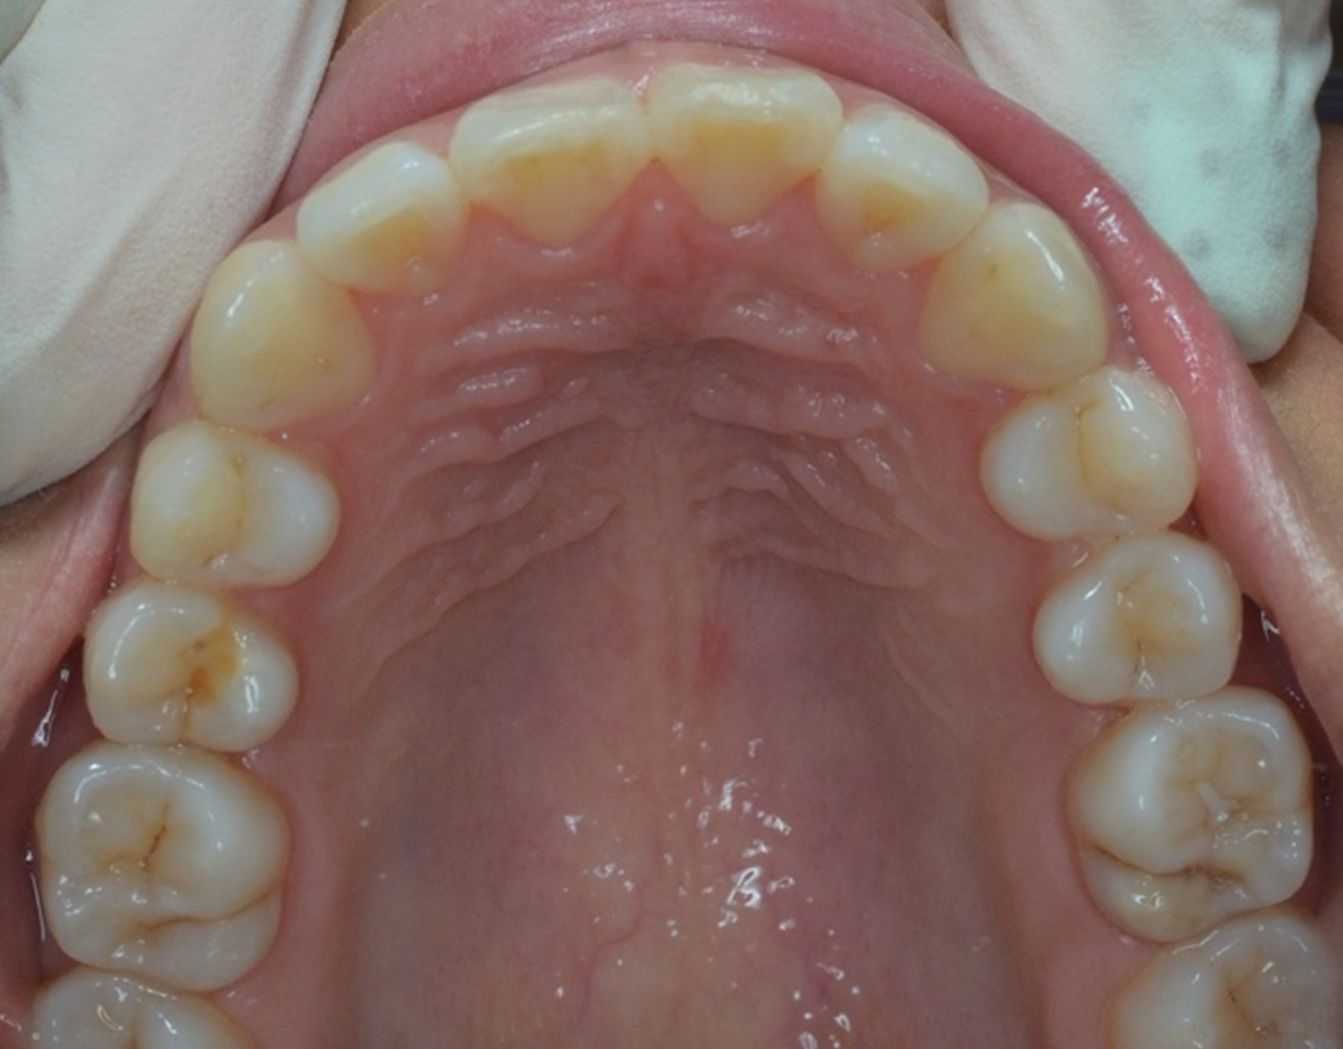

A continuación, mostramos el caso de una paciente adulta con clase II ósea y dentaria.

Con Ortodoncia Invisible, y gracias a la cooperación de la paciente, conseguimos este resultado y, lo más importante de todo, que la paciente sonría sin complejos.